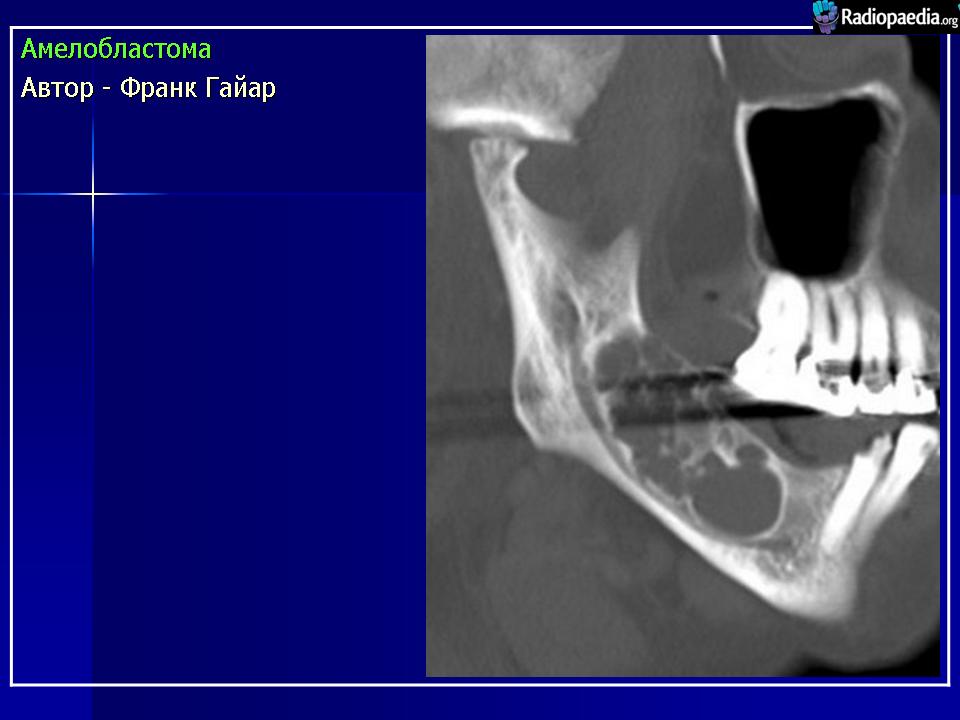

Амелобластома

ID: 9430 Ameloblastoma Dr Frank Gaillard - 16 Apr 2010 Ameloblastoma resected en-blocAuthor: Berto1286Original files:http:...